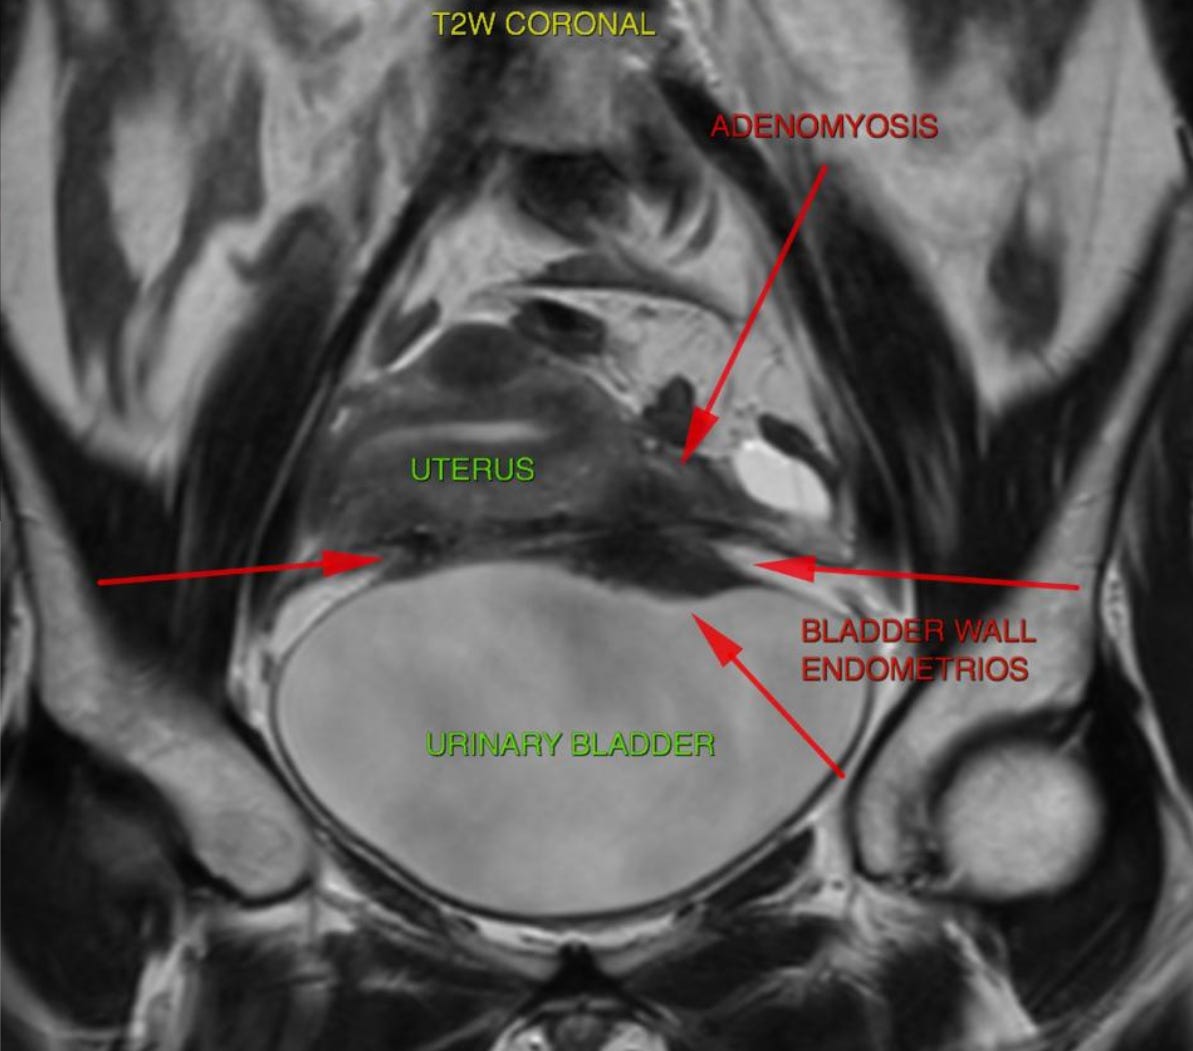

Here’s a similar nodule from a different plane. This is along the coronal plane.

Mapping well is the first step to preparing for a successful surgery. Pro tip: Make sure your radiologist reports for:

Lesion Size and Location

Depth of detrusor muscle invasion

And distance from UVJ (Uterovesical Junction)